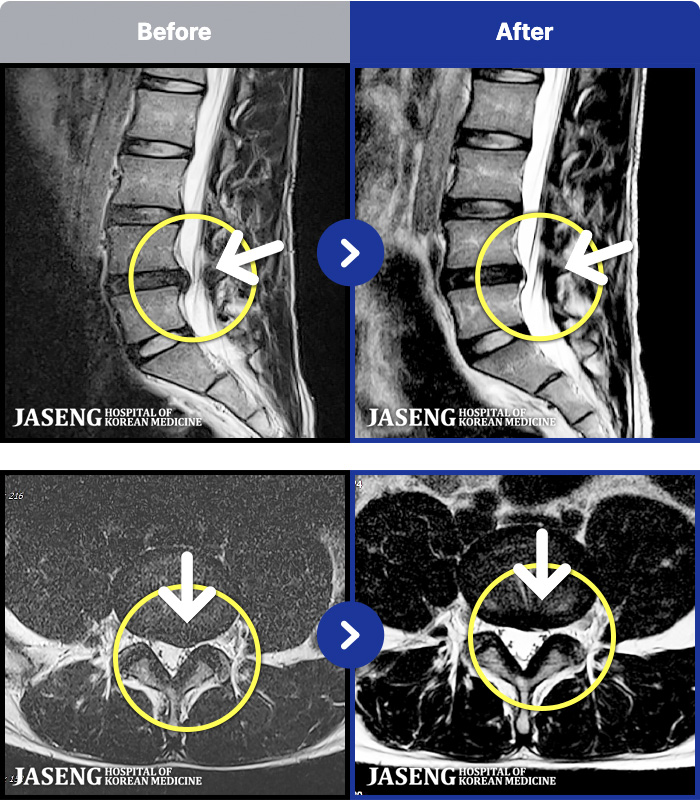

ȯںп Ǹ ǿ ԿǾ, ο ġ ۿ Ƿ ġḦ Ͻñ ٶϴ.